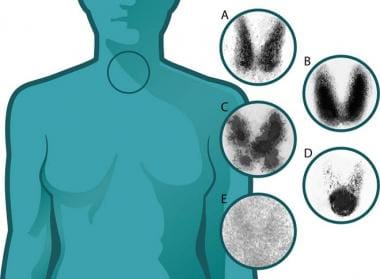

Radioactive iodine uptake test Wikipedia shop, Radioactive iodine uptake Information Mount Sinai New York shop, Radioactive Iodine Uptake Test shop, Radioactive Iodine Uptake Testing Background Indications shop, Radioactive Iodine Uptake Test Risks Preparation and Results shop, Radioactive Iodine Uptake And Scan My Endo Consult shop, Radioactive Iodine Columbia Surgery shop, Radioactive Iodine Uptake Test MEDizzy shop, Radioactive Iodine RAI Uptake THANC Guide shop, A radioactive iodine uptake test A B C and D demonstrate shop, StudyXing Medicine on X shop, Radioactive iodine uptake RAIU test shows large right and left shop, Radioactive Iodine Therapy to Treat Thyroid Cancer shop, AMBOSS Step2CK quiz time Can you distinguish the shop, Thyroid Scintiscanning an overview ScienceDirect Topics shop, Hyperthyroidism and Thyrotoxicosis Workup Approach Considerations shop, Radioactive Iodine Uptake Test Health Library NewYork Presbyterian shop, Twenty four hour radioactive iodine 123 uptake test. The images shop, Graves Disease Endocrine Medbullets Step 2 3 shop, Radioactive Iodine Uptake Testing Background Indications shop, Radioactive Iodine Uptake Test Risks Preparation and Results shop, Hyperthyroidism Diagnosis and Treatment AAFP shop, Thyroid Cancer SNMMI shop, Radioactive Iodine RAI Uptake THANC Guide shop, Thyroid Scan and Uptake shop, Determination of remnant thyroid volume comparison of shop, Solved Radioactive iodine uptake Normal adult 16 yr. old Chegg shop, Radioactive Iodine Uptake and Scan in Various Forms of shop, Radioactive iodine uptake shop, RADIOACTIVE IODINE UPTAKE TEST Text in List. Doctor Looking for shop, Thyroid Scan and Uptake RadiologyInfo shop, Radioactive iodine uptake shop, Thyroid Scan in Bangalore Nuclear Scan Manipal Hospitals shop, PatEdu Thyroid Surgery shop, Iodine Whole Body Scan Test Price In Delhi Cost Near Me India shop.

Radioactive Iodine Uptake Test

Radioactive Iodine Uptake Testing Background Indications